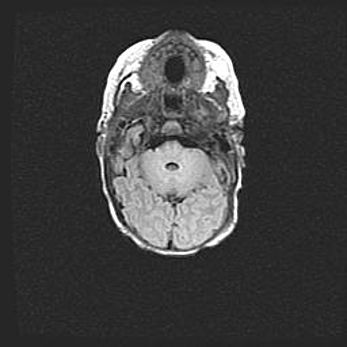

Подострая гематома правой гемисферы мозжечка.

Наружная гидроцефалия.

Возраст: 15 дней

Вес: 3100 г

Пол: женский

Окружность головы: 37 см

Срок гестации: 35-36 недель

При открытой наружной форме гидроцефалии у новорожденных расширяются и переполняются субарахноидные пространства.

Кровоизлияния в мозжечок имеют две клинико-анатомические формы: полушарные гематомы и кровоизлияния в червь.

К появлению этой патологии может привести: повреждения головного мозга, возникающие в результате асфиксии и гипоксии плода при беременности, или травмы во время родов. Редко гематома мозжечка может быть результатом первичной коагулопатии и сосудистой мальформации, диссеминированном внутрисосудистом свертывании, изоиммунной тромбоцитопении.